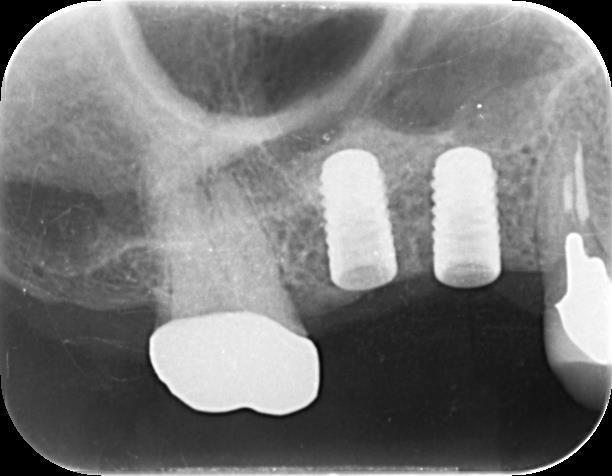

右上の歯がないところを、骨を足してインプラントで回復

右上の歯がないところをインプラントで回復した症例を紹介いたします。

骨が少なくてソケットリフトという方法を用いて骨を足す必要がありましたが、上手くいって

インプラントは現在も経過良く維持しており、嬉しく思います。

インプラントの歯はCERECというコンピュータを使って、機械でセラミックの歯をつくりました。

レントゲンのインプラントの上の部分の少し白いやつが

足してあげた骨です。

インプラントの上には上顎洞というお鼻の空洞があり

インプラントの強さを増すために同部に骨を足す必要が

あったからです。